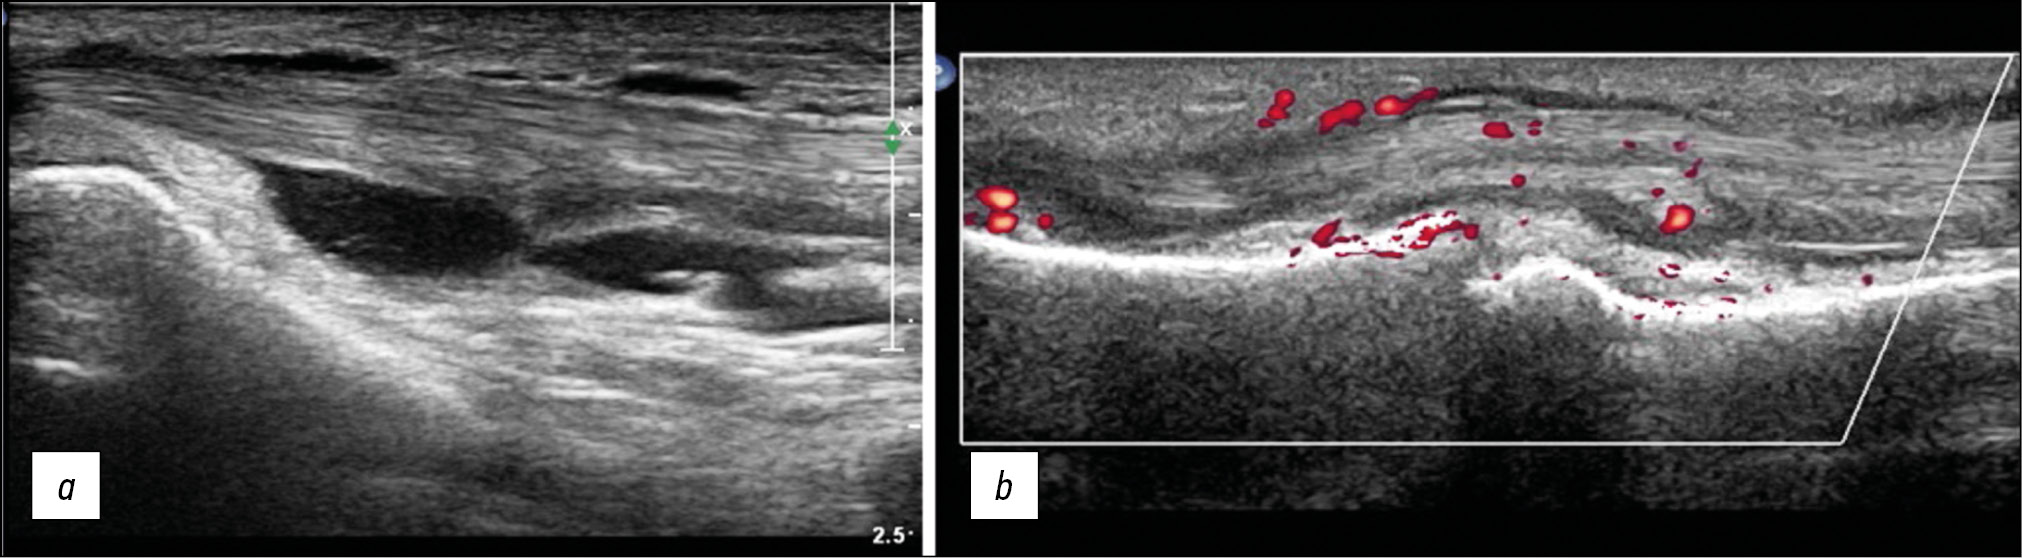

Skeletal muscle injuries detected in the intensive care unit were characterized by muscle wasting and functional impairment. In 32 patients (93.8% men, mean age 64.1±12.6 years) with severe COVID-19, skeletal muscle mass and functional parameters were assessed within 24–72 hours after hospitalization. US images were taken of the rectus femoris cross-sectional area, anterior quadriceps thickness (rectus femoris and medial vastus), and echogenicity. During follow-up at 10 days, a significant decrease in the cross-sectional area of the rectus femoris (–30.1%; p <0.05), thickness of the anterior quadriceps muscle (–18.6%; p <0.05), and grip strength (–22.3%; p <0.05) were reported. After transfer from the intensive care unit, none of the patients returned to normal physical activity levels [19]. US imaging data obtained at the N.N. Priorov National Medical Research Center of Traumatology and Orthopedics illustrate the processes occurring in the muscles with undernutrition (Fig. 2).

Fig. 2. Cross-sectional ultrasound of muscular hypotrophy (a), comparison with the healthy side (b). The muscle volume is reduced with increased echogenicity, and differentiation into fibers is preserved.